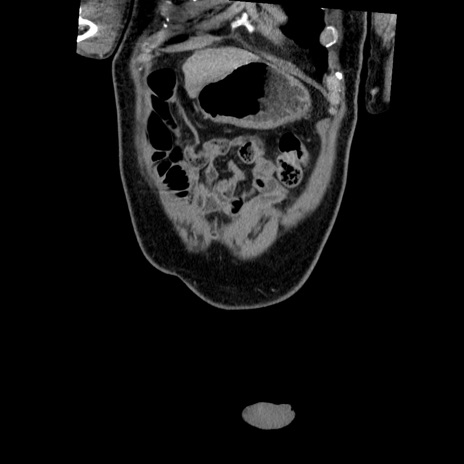

症例

【症例】50歳代男性

【主訴】腹痛

【現病歴】AVMからの被殻出血のため回復期リハ病棟入院中。 本日午後3時頃急に下腹部痛が出現した。

【既往歴】AVM、被殻出血、虫垂炎、高血圧

【身体所見】意識晴明、左半身不全麻痺、会話の理解は良好、36.5°C、腹部:膨隆、全体に板状硬、下腹部正中に圧痛点あり、反跳痛-、筋性防御不明、右下腹部にope scar

【データ】WBC 9400、CRP 0.06

横断像